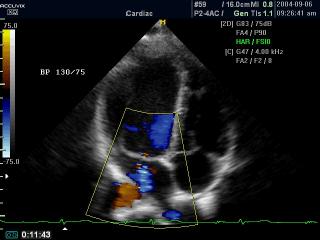

Регургитация митрального клапана, цветной допплер

Accuvix-XQ. Регургитация митрального клапана, цветной допплер (videо).